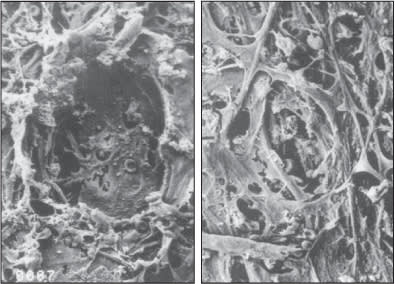

The lack of repeatability of ALT prompted the study and ultimate introduction of SLT. Unlike ALT, SLT uses much lower energy and thus does not cause irreversible tissue scarring (Figure 1).

Figure 1. ALT histology (left) shows permanent trabecular mesh-work damage while SLT histology shows no destruction of the trabecular meshwork.